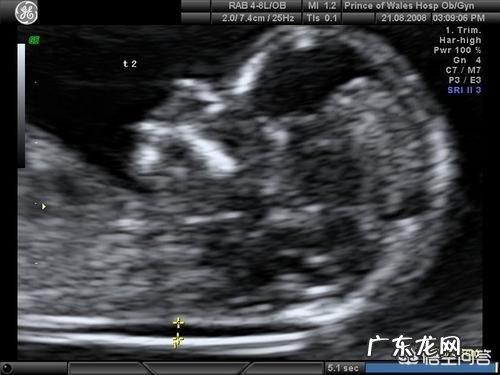

方法不同1、早期唐筛一般是指NT检查,就是B超做颈后透明带扫描,有的医院也会让抽血化验唐筛,我当时只做了NT 。

关于早期唐筛早唐其实是两个项目,一个抽血检查一个NT筛查,抽血检查需要空腹,NT筛查是通过B超测量胎儿后颈项透明层厚度,数值≤3mm为正常 。建议在11周~13(+6天)周做检查,过早过晚都有可能导致数据不准确,值得注意的是,此次筛查结果仅供参考,并不是确诊依据 。